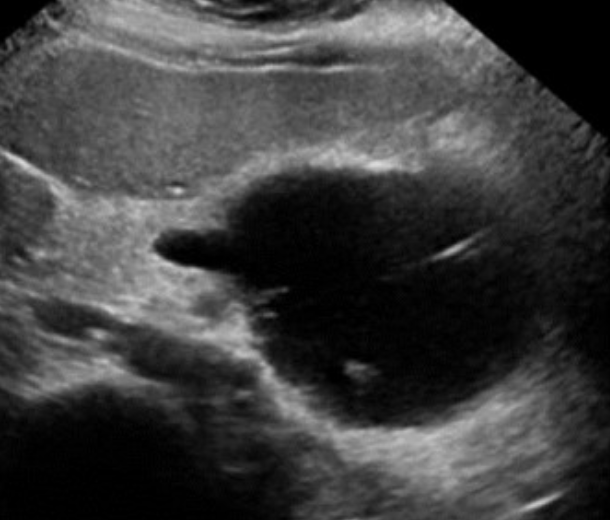

AAA (Abdominal Aortic Aneurysm) → focal dilation of aorta

2D US presentation: focally dilated AO (3 cm or greater), mural hypoechoic thrombus, wall calcifications, usually located infrarenal, can be fusiform or saccular

color doppler: turbulent helical flow

DDX: aortic dissection (aorta may be enlarged, but has intimal flap), pseudoaneurysm (focal outpouching w/ narrow neck, but not all 3 layers involved)